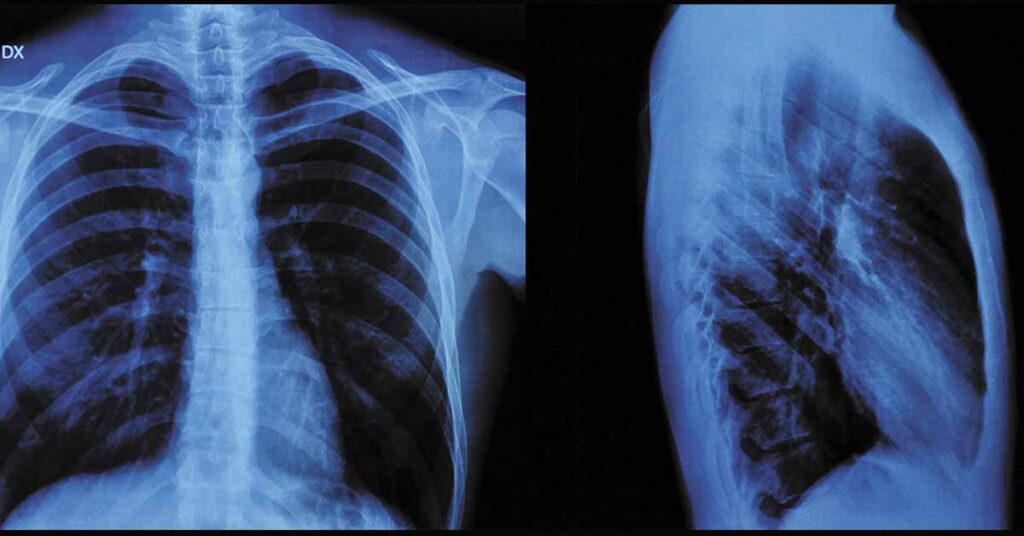

O raio X do tórax é um exame de imagem amplamente utilizado para avaliar pulmões, coração e outras estruturas da região torácica, sendo fundamental na identificação de infecções e inflamações respiratórias. Trata-se de um método rápido, seguro e acessível, que auxilia médicos no diagnóstico e no acompanhamento de diversas condições clínicas.

O raio X do tórax é um exame de diagnóstico por imagem que utiliza baixas doses de radiação ionizante para produzir imagens das estruturas internas do tórax.

Essas imagens permitem a visualização detalhada dos pulmões, do coração, das costelas, da coluna torácica e do mediastino.

O princípio do exame baseia-se na diferença de absorção dos raios X pelos tecidos do corpo. Estruturas mais densas aparecem mais claras na imagem, enquanto áreas com ar, como os pulmões saudáveis, tendem a ser mais escuras.

Alterações nesse padrão auxiliam na identificação de processos patológicos.

Em casos de infecções respiratórias, como pneumonia ou tuberculose, o exame pode revelar áreas de consolidação pulmonar ou padrões sugestivos de acometimento infeccioso.

O exame também auxilia na detecção de inflamações pulmonares, derrame pleural e outras alterações inflamatórias que modificam a aparência normal das estruturas torácicas.